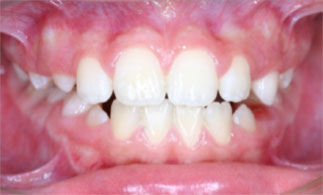

(example of a crossbite)- Upper back teeth are

located behind Lower back teeth